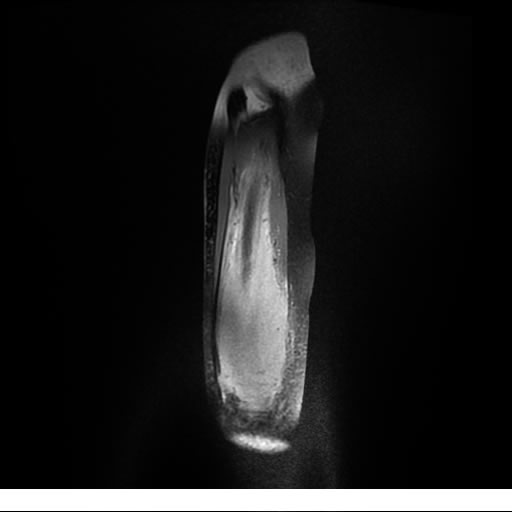

Se realiza estudio de MRI de muslo izquierdo en diferentes planos, con secuencias de Spin Echo, GRE; ponderadas a T1 y a T2, se utilizan pulsos de saturación de grasa y se administra medio de contraste IV a base de Gadolinio en base al peso del paciente.

La diáfisis femoral izquierda muestra reacción perióstica importante, se extiende desde el cuello del fémur, invade trocánteres, diáfisis femoral, medial y distal, es compatible con un proceso infeccioso óseo, el complejo muscular del muslo se ve edematizado.

Hallazgos en Resonancia Magnética (RM)

La resonancia es la modalidad de elección para valorar la extensión intramedular y la infiltración en tejidos blandos, brindando una imagen más detallada del compromiso tumoral. Los hallazgos característicos incluyen:

Lesión de señal heterogénea en secuencias T1 (hipointensa) y T2/STIR (hiperintensa), que refleja necrosis, hemorragia y contenido celular diverso.

Realce intenso y heterogéneo tras la administración de contraste (gadolino), lo que indica vascularización tumoral.

Compromiso de la médula ósea adyacente y de estructuras vecinas, como músculos y neurovasculatura.

Posible presencia de edema óseo y necrosis central.